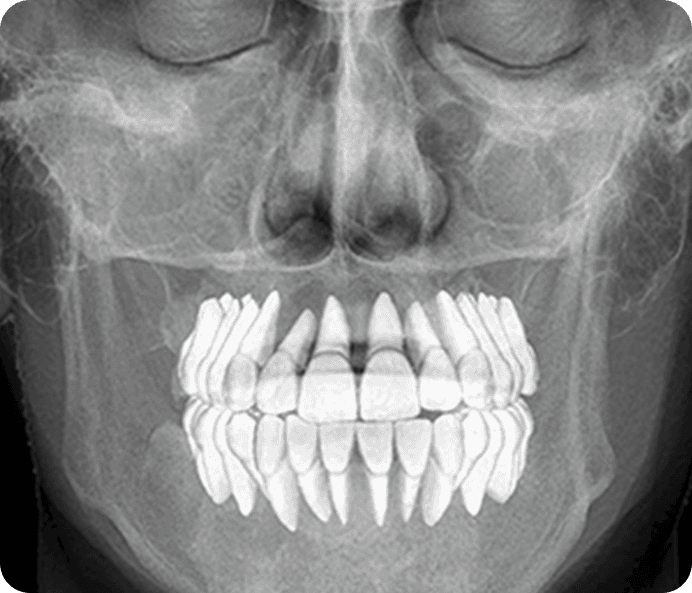

CBCT, OPG and CEPH

3D Imaging For Clearer Diagnosis And Planning

CBCT, OPG, and CEPH scans help our specialists examine teeth, bone support, jaw structure, and surrounding areas in greater detail. This advanced dental imaging is especially useful for dental implants in Hyderabad, orthodontic treatment planning, oral surgery, and other complex dental concerns.